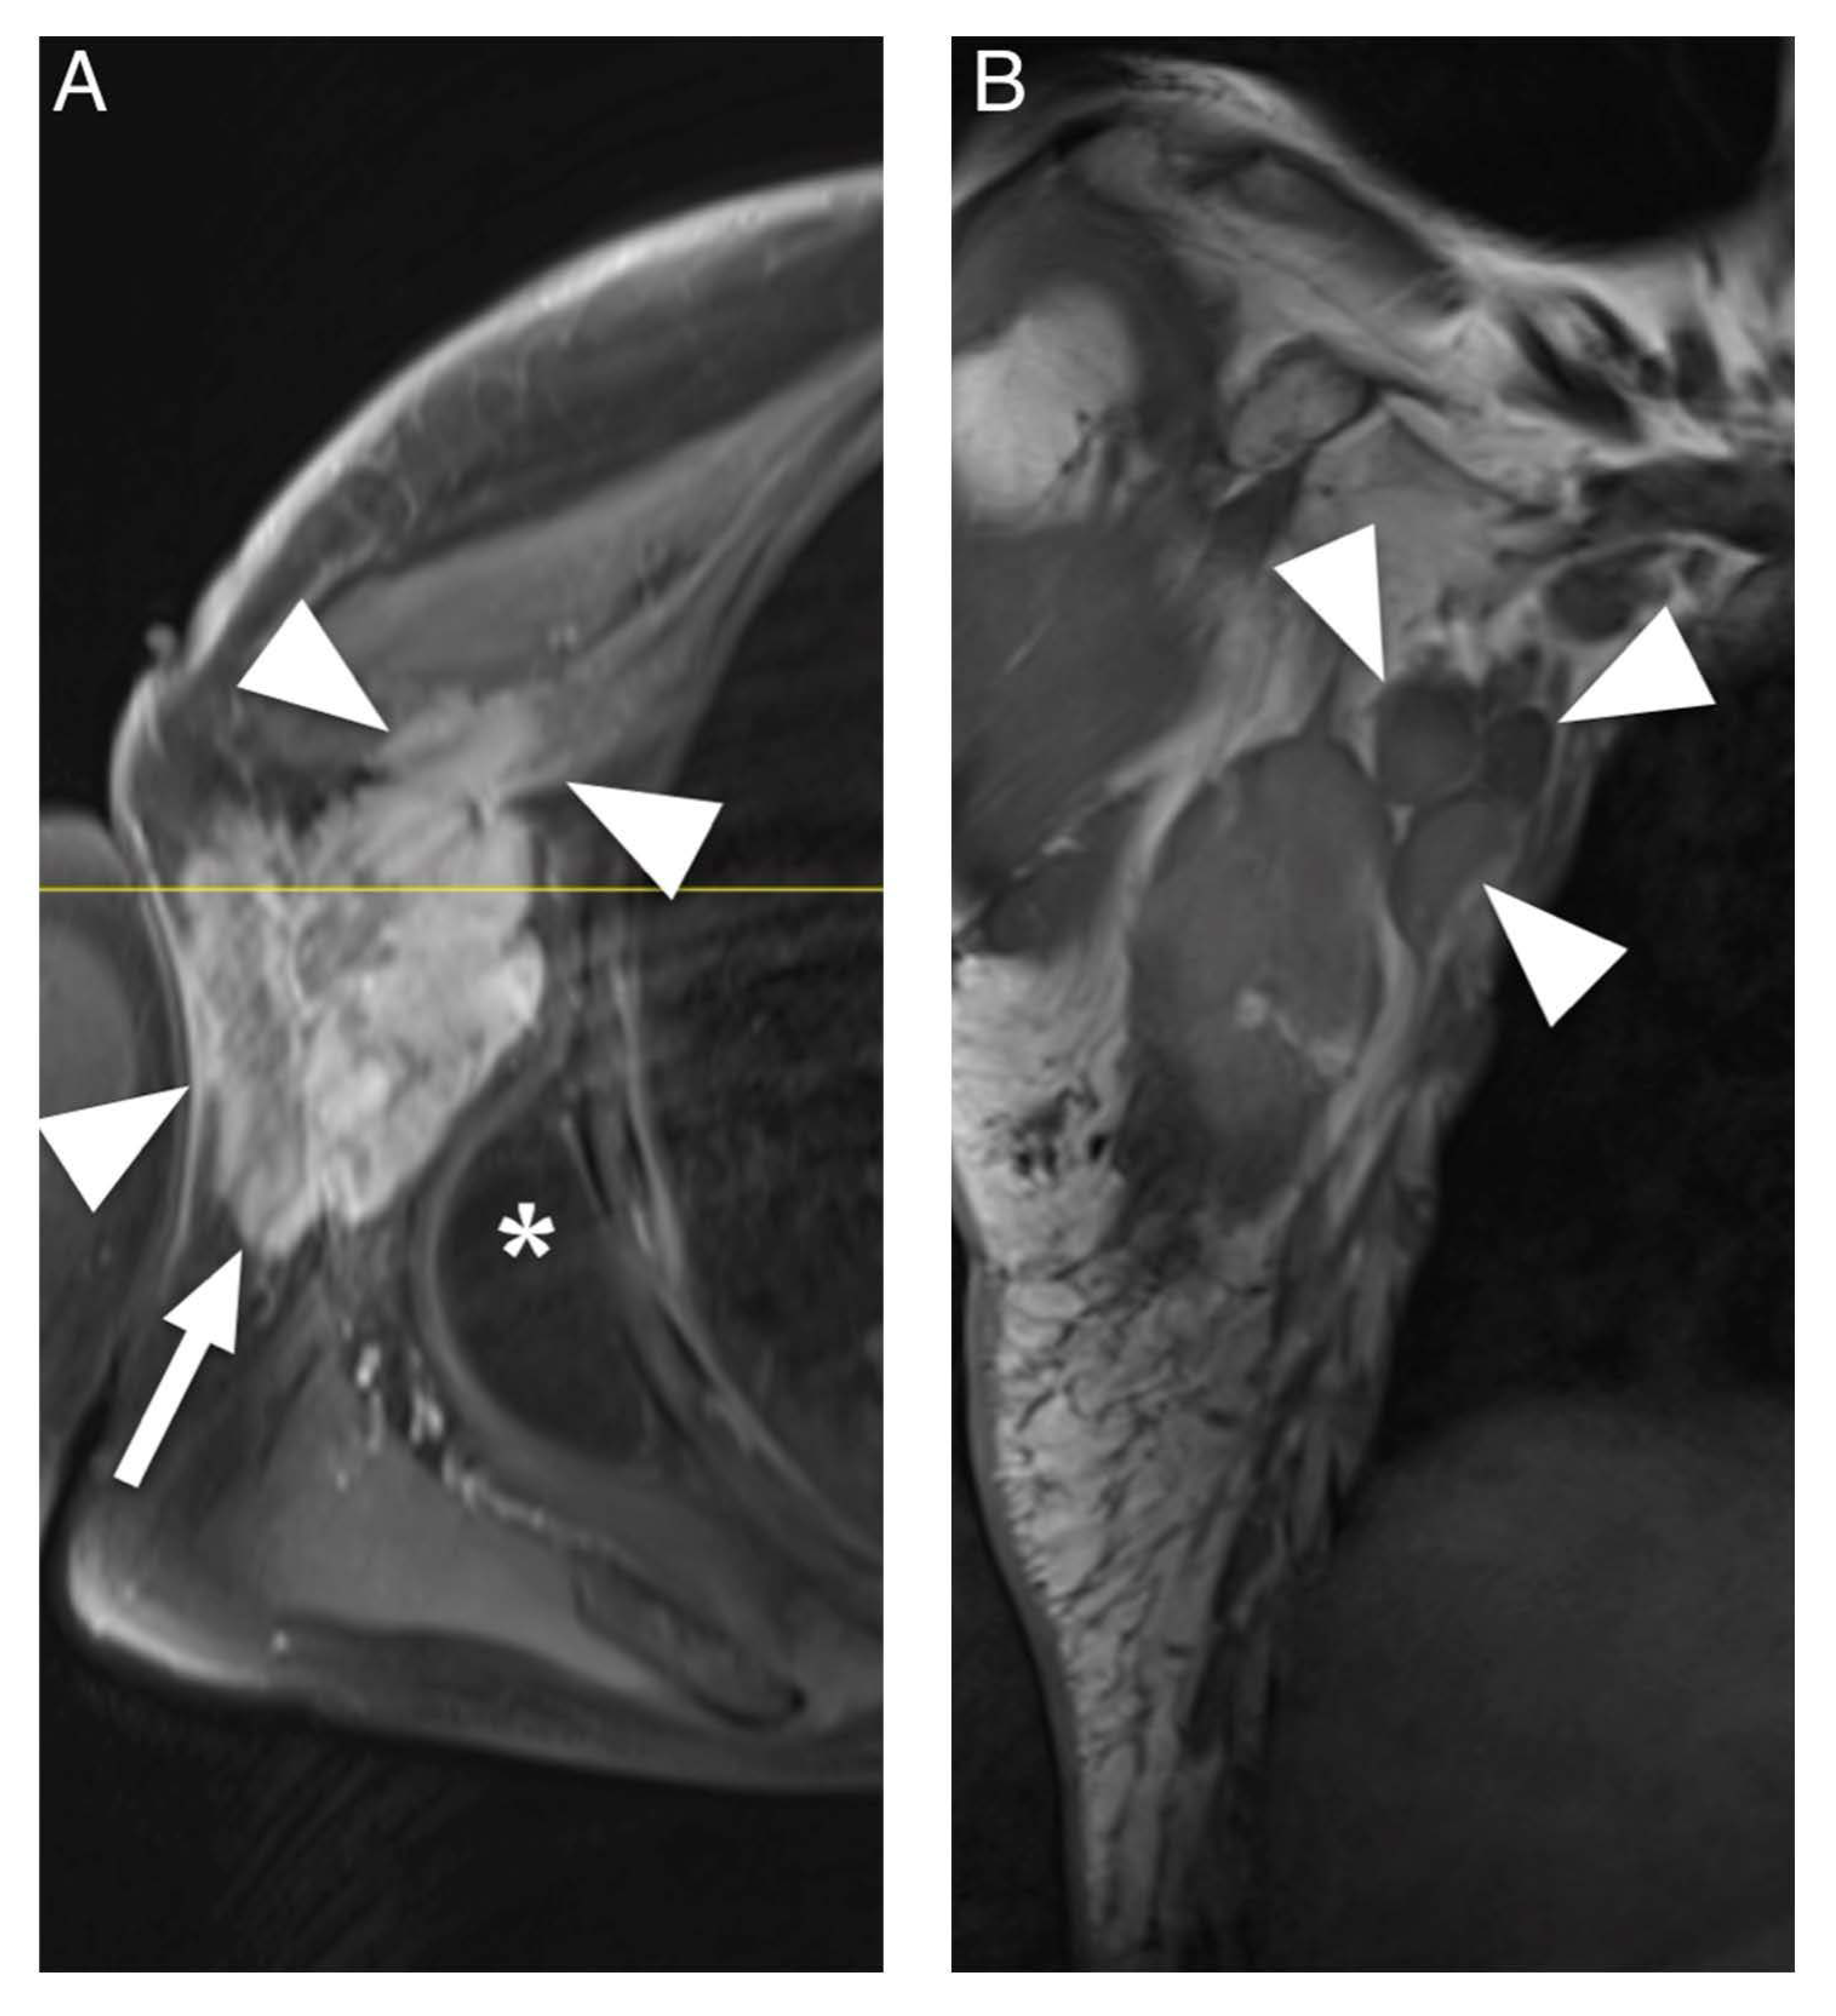

4. Discussion